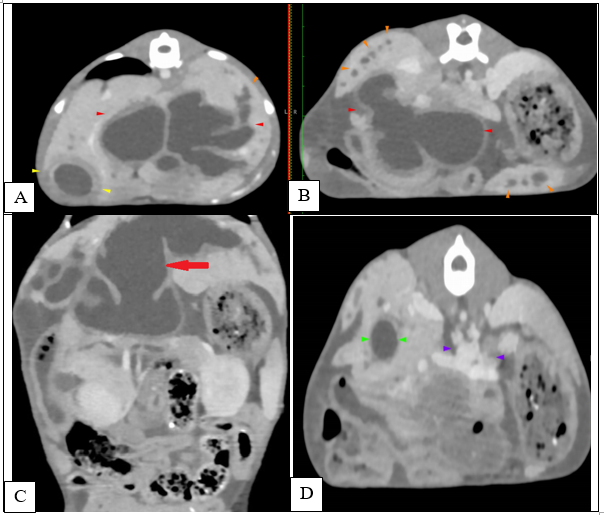

At the age of 4 months, a dual-phase (portal and delayed-venous) abdominal CT was performed to further describe the lesions and the extent of the process (SOMATON Scope CT VC40, 16-slice CT, Siemens, USA). A non-ionic iodinated contrast agent consisting of iohexol (Omnipaque™, GE Healthcare) was administered via an intravenous bolus. Post-contrast results of the examination were represented by hepatomegaly with large tubular structures, non-enhancing and hypoattenuating to the surrounding parenchyma, present throughout the liver (Figure 4A, C-red arrowhead). The tubular structures follow the approximate location of the biliary ducts with a branching pattern within the liver, close to the hepatic vasculature. (Figure 4A, B-orange arrowhead). There was difficulty encountered in identifying the gallbladder, as a result of numerous distended loops (Figure 1A-yellow arrows). A 9 mm, large, distended structure extending throughout the right limb of the pancreas to the region of the duodenal papilla was noted (Figure 4D-green arrows). The pancreatic duct was mildly distended, measuring less than 3 mm in diameter. The distended structures were filled with fluid attenuation content (10 – 20 HU) with a variably thickened wall (less than 4 mm). The hepatic changes had a marked mass effect, with right-sided displacement of the caudal vena cava noted due to the mass effect of hepatic changes. The mesenteric vasculature was relatively prominent, with many tortuous vessels present medial at the left kidney in the region of the left gastric vein and cranial mesenteric artery (Figure 4D-purple arrows). There was no evidence of a single well-defined congenital extrahepatic or intrahepatic shunt.

Figure 4 Transverse (A, B, D) and coronal (C) abdominal CT 0.75 mm slice image- Distended intrahepatic ducts causing a mass effect at the level of the cranial abdomen (red arrow) and pancreatic cyst (green arrow). A mild peritoneal effusion was noted, although this finding was unremarkable for the age of the patient.